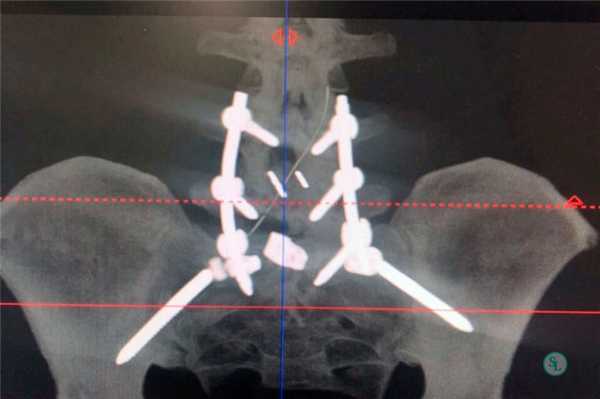

Стабилизационная система на рентгене.

В большинстве случаев проблемный сегмент стабилизируют с помощью металлоконструкций, чаще представленных транспедикулярными системами и пластинами с винтами из высокотехнологичных сплавов металла. В хирургии такая техника называется инструментацией позвоночника. Кроме металлоконструкций, для стабилизации также могут быть применены полимерные устройства, сделанные, например, из углеводородного волокна или резорбирующегося высокомолекулярного биополимера. К отдельной разновидности стабилизирующих вмешательств, которые не причисляют к инструментации, относят установку кейджей имплантатов межпозвоночных дисков.

Системы стабилизации позвоночника жесткого типа

Жесткие, или неподвижные металлоконструкции подразумевают закрепление позвонков в постоянном фиксированном положении. Устанавливаются они из заднего доступа (со стороны спины) под контролем КТ и рентген-аппаратуры. Крепятся к позвонкам резьбовыми винтами, которые погружают в костные тела на глубину до 80%. Рекомендуют ставить подобного плана системы сугубо в безальтернативных случаях, если ни один другой вид лечения не сможет решить проблему с поврежденным отделом позвоночника.

Стабилизация поясничного отдела.